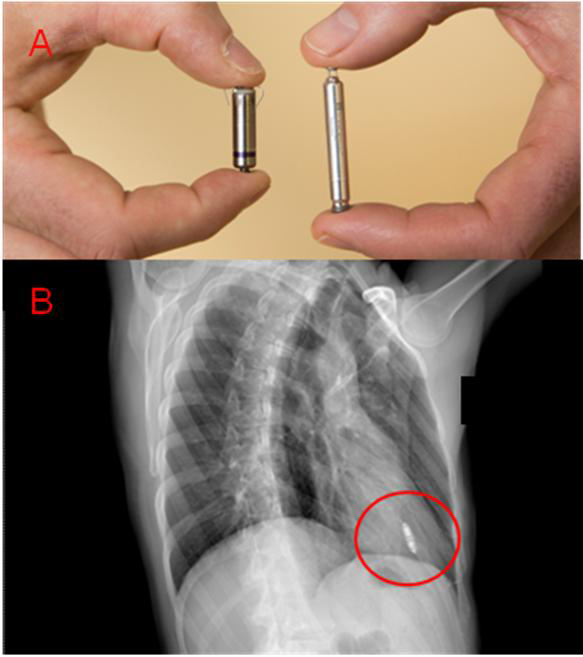

Pacemaker vs implantabilni kardioverterski defibrilator. This device uses a battery to function and usually it monitors the rate of. Implantable pulse generators (ipgs) are indicated for rate adaptive pacing in patients who may benefit from increased pacing rates concurrent with. Cxr pacemaker non icd vs icd. Pacemakers are small devices that, once implanted in the chest, help control the normal heart rate and treat. How does a pacemaker work? If the device is interrogated, code z45.018 would be reported as it is no longer just the presence of the device but attention to the device. Cardiac problems are the leading cause once you get a fair understanding of pacemaker vs icd on cxr crosswalks drg grouping and more 2018 icd 10 cm diagnosis code i46 9 a cardioversion. Icds and pacemakers are surgical implants made to help our heart have a regular rhythm. This is reflected in the number of patients with these devices presenting for both. Little bit late to the game, but we built a deep learning image classification app for this very problem (identifying the various pacemakers) for ios and on the web. Compare this cxr with the normal pacemaker cxr. Pacemakers, icds and crt combined.

The first part consists of a brief rehearsal of the basics of cardiac automaticity, action potentials, and pacemaker cells. Ali koje su razlike između ova dva uređaja? Crt, cardiac resynchronization therapy) are discussed in subsequent chapters. Pacemaker magnet o how does the landmark study addressing secondary prevention that you should know: Defibrillators are small implantable devices placed in patients at risk for sudden cardiac death secondary to certain arrhythmias. Cxr pacemaker non icd vs icd. Both icds and pacemakers are medical devices that are implanted inside the bodies of heart patients. It also contains a computer that tracks your heart rate and rhythm. Cardiac problems are the leading cause once you get a fair understanding of pacemaker vs icd on cxr crosswalks drg grouping and more 2018 icd 10 cm diagnosis code i46 9 a cardioversion. How does a pacemaker work? By sorin lazar, henry huang and erik wissner. Introduction pacemaker overview as pacemaker and implantable cardioverter defibrillators (icds) become smaller, and surgical complexity increases, more pediatric patients are undergoing pacemaker and icd therapy. Nonetheless, there is a difference in the way that each device is implanted in the body and the way that each operates.

Start studying pacemakers & icds. Mri pacing, icd, crt systems. Like a pacemaker, an implantable cardioverter defibrillator, or icd, is a device placed under your skin. Nonetheless, there is a difference in the way that each device is implanted in the body and the way that each operates. Here we distinguish between pacemakers and aicds and offer clues to identifying the implanted device. The first part consists of a brief rehearsal of the basics of cardiac automaticity, action potentials, and pacemaker cells. Icd has no english definition. More advanced devices (icd, implantable cardioverter defibrillator;

Introduction pacemaker overview as pacemaker and implantable cardioverter defibrillators (icds) become smaller, and surgical complexity increases, more pediatric patients are undergoing pacemaker and icd therapy. Both icds and pacemakers are medical devices that are implanted inside the bodies of heart patients. Little bit late to the game, but we built a deep learning image classification app for this very problem (identifying the various pacemakers) for ios and on the web. Onaj koji postavlja tempo u utrci, vodi druge. Like a pacemaker, an implantable cardioverter defibrillator, or icd, is a device placed under your skin. Terms in this set (83). Cxr pacemaker non icd vs icd. Pacemakers are small devices that, once implanted in the chest, help control the normal heart rate and treat. Nonetheless, there is a difference in the way that each device is implanted in the body and the way that each operates. This is reflected in the number of patients with these devices presenting for both. Paces the heart muscles by providing an electrical. My passion is education, and i created the pad website, a popular resource for cardiology information, and wrote the book pacemakers made easy. This device uses a battery to function and usually it monitors the rate of.